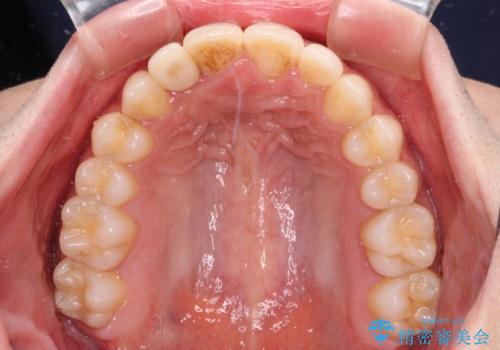

- 上下前歯のデコボコを気にして来院された患者様です。

前歯のセラミックが装着されている歯は、歯根が短くなっており、他院では抜けてしまうので矯正はできないと言われていたようです。

患者様と相談し、抜けてしまった場合にはインプラントあるいはブリッジによる補綴治療が必要となることを確認し、極力歯根に負担のかからないような仕上がりで治療を進めて行くこととしました。

デコボコを解消には、IPR(歯と歯の間を削る)をメインに歯列排列を設計し、インビザラインにて矯正治療を行うこととしました。

レントゲン写真上では、矯正治療前後で歯根長さに大きな違いはなく、抜歯を回避することができました。

上顎内側に転位している前から2番目の歯は移動が難しく、無理矢理歯根全体を動かそうと設計すると、歯肉退縮・歯髄壊死・歯根吸収といった危険性が増すため、無難なゴールにて治療を終えることとなりました。